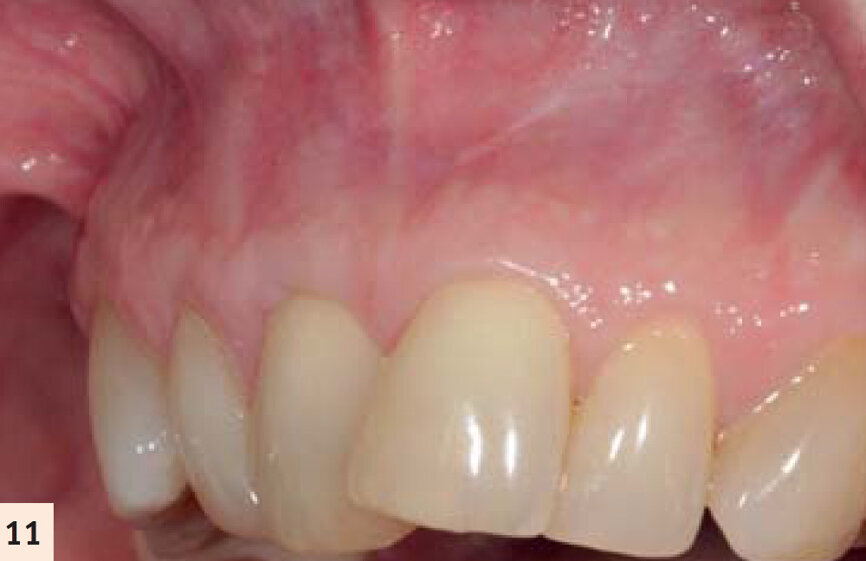

figure 11 : Vues pré- et postop (2 ans). Noter l’augmentation tridimensionnelle de la zone de tissu kératinisé et attaché, ayant pour résultat la restauration de la perte d’attachement et la correction de la

déformation gingivale en hauteur et en largueur.